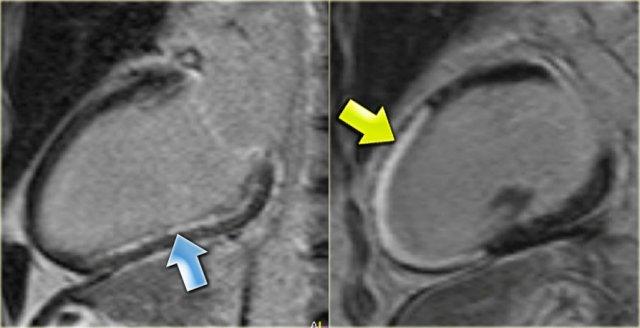

Trái: Hình ảnh ngấm thuốc muộn góc nhìn 3 buồng cho thấy sự ngấm thuốc của vách liên thất nền phì đại (mũi tên)

HOCM (3)

Ở ngoài cùng bên trái là hình ảnh ngấm thuốc muộn góc nhìn 3 buồng, minh họa rõ ràng sự ngấm thuốc của vách liên thất nền phì đại (mũi tên).

Bên cạnh đó là hình ảnh ngấm thuốc muộn trục ngắn cho thấy sự ngấm thuốc điển hình tại các điểm bám của thất phải ở phía trước và phía sau (các mũi tên).

Hình ảnh ngấm thuốc muộn góc nhìn 3 buồng trước (trái) và sau (phải) đốt cồn. Lưu ý nhồi máu xuyên thành của vách liên thất nền (mũi tên).

Điều trị HOCM bao gồm điều trị nội khoa, phẫu thuật cắt cơ tim hoặc đốt cồn [15].

Kết quả của đốt cồn được mô tả rất rõ ràng trên MRI [19].

Bên trái là hình ảnh ngấm thuốc muộn góc nhìn 3 buồng trước và sau đốt cồn.

Lưu ý nhồi máu xuyên thành của vách liên thất nền (mũi tên).